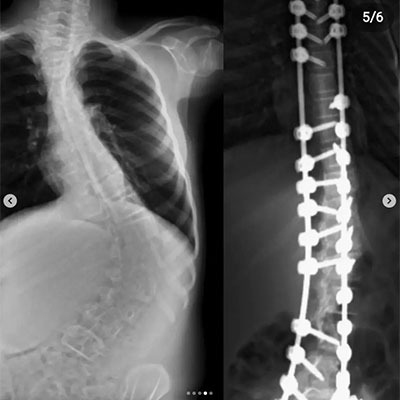

Skolyoz, omurganın yandan bakıldığında S veya C şeklinde eğrilik gösterdiği bir omurga hastalığıdır. Genellikle çocukluk ve ergenlik döneminde başlayan bu durum, omurganın düzgün hizalanmasını engeller. Skolyozun nedeni tam olarak bilinmese de, çevresel, genetik veya nöromüsküler faktörlerle ilişkili olabileceği düşünülmektedir. Hafif vakalardan ciddiye kadar değişen şiddette görülebilir ve bazı durumlarda belirti vermeden ilerleyebilir. Ancak ilerleyen vakalarda, omurga eğriliği ve eşlik eden postür bozukluğu nedeniyle fiziksel rahatsızlıklara, sırt ve bel ağrısına, solunum güçlüklerine ve organlara baskıya neden olabilir. Erken teşhis ve tedavi, skolyozun ilerlemesini engellemeye ve yaşam kalitesini artırmaya yardımcı olabilir.

Omurganın ön ve arkadan bakıldığında 8 - 10 derece üzerindeki sağ veya sol tarafa olan eğriliği ile buna eşlik eden, kendi ekseni etrafındaki dönme hareketinin (rotasyon ) oluşturduğu bir şekil bozukluğudur. Skolyoz omurga deformiteleri içerisinde en sık karşılaştığımız ve ilerleyen evrelerde ciddi duruş bozukluklarına neden olan üç boyutlu bir omurga deformitesidir.